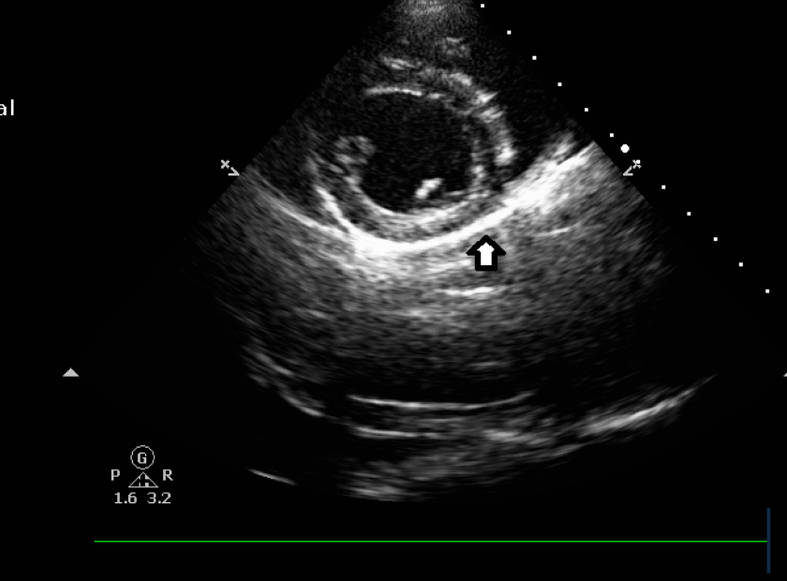

A ecocardiografia veterinária é um exame de imagem que avalia em tempo real a anatomia e o funcionamento do coração. Utilizada principalmente em cães e gatos com suspeita de doenças cardíacas, ela permite observar o fluxo sanguíneo e a força das contrações cardíacas. Trata-se de uma ferramenta essencial para o diagnóstico precoce e o acompanhamento de tratamentos na área da cardiologia veterinária.

A ecocardiografia é realizada com o animal em posição lateral, utilizando um equipamento de ultrassom especializado que avalia as câmaras cardíacas, válvulas e fluxo sanguíneo. O exame é indolor, não invasivo e fornece informações essenciais sobre a função cardíaca. Ele é indicado tanto para diagnóstico inicial quanto para acompanhamento de tratamentos em andamento.